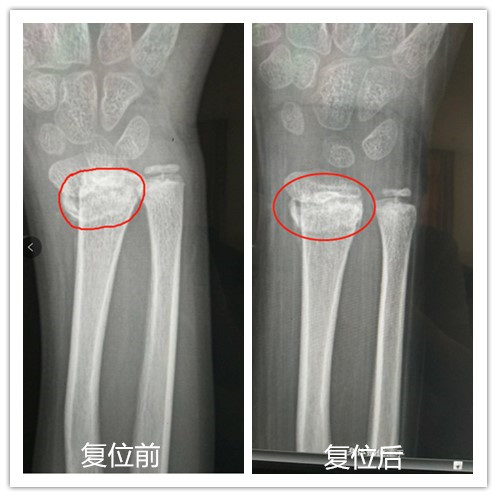

经过综合评估,陈国富主任运用精湛熟练的正骨手法为乐乐进行了接骨,只用了5秒钟,手法复位顺利结束,DR摄片显示骨折处对位对线良好,陈主任也松了一口气:“孩子的骨折复位良好,将来不会存在功能受限症状。”陈国富主任说,“正骨复位好是一次就达到满意的效果,多次反复的整复,往往会加重局部软组织的损伤,使受伤部位肿胀更加严重,而且有造成骨折愈合延迟或关节强硬的可能。”

复位结束后,陈国富主任对乐乐的后期康复进行了指导,建议乐乐要充分的练习腕关节的活动,对防止肌腱粘连很有帮助。乐乐妈妈观看了术后复位的ct片,对治疗效果非常满意,感叹道,幸好来找到了陈国富主任,复位及时、精准,不然后果不堪设想。